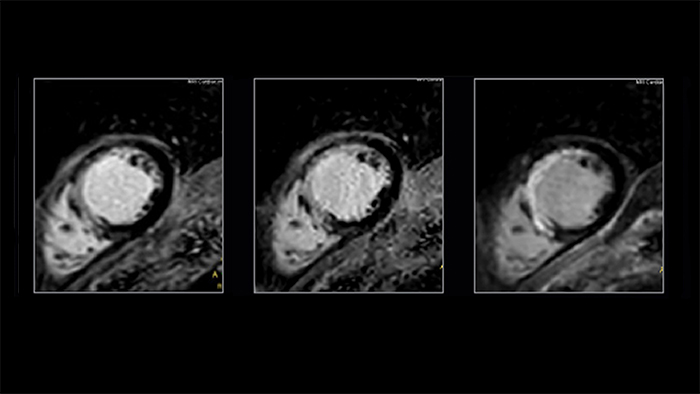

Compressed SENSE has also enabled a change in strategy when scanning our most challenging patients: moving to 3D LGE acquisitions. A 3D whole-heart breath hold in approximately 11 seconds (depending on HR) has been enabled by combining Compressed SENSE with additional signal afforded by 2-echo mDIXON, which also allows water-only and fat-only image reconstruction (see Fig. 2).

Figure 2. In LGE C-SENSE can accelerate 2D and 3D acquisitions. Left to right: free-breathing single-shot SENSE x2, free-breathing single-shot C-SENSE x3 – a shorter readout provides a sharper image, equivalent slice from 3D mDIXON C-SENSE x6 breath hold (13s at 70bpm)

Conventional SENSE acceleration is still an established and reliable scan acceleration method. For patients with good breath holding capacity, conventional SENSE is still sometimes preferred. But for patients whose clinical history limits their ability to breath hold (e.g. bradycardia, COPD, heart failure, pleural effusion), Compressed SENSE is a very effective option and can be considered a highly efficient tool in a cardiac MR radiographer’s armory for circumstances where the patient’s compliance or cardiac rhythm is not optimal.